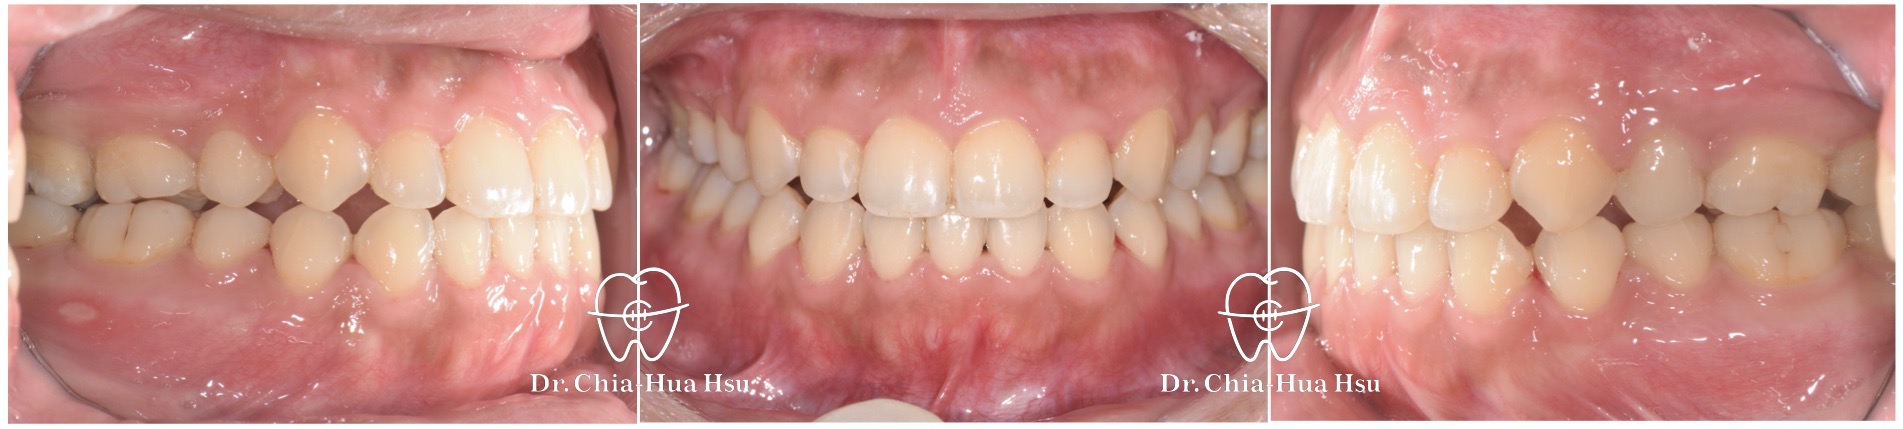

- 病患主訴:牙齒凌亂擁擠、笑的時候看到牙齦。

- 問題分析:患者是屬於長臉型,有笑齦問題、齒列擁擠以及先天性缺失下顎門牙一顆(下顎三顆門牙)。

- 治療方式:使用傳統金屬矯正器,拔除上顎兩顆小臼齒以獲得空間,並搭配上顎骨釘的使用,改善笑齦問題。

- 治療結果:齒列排齊,改善笑齦 ; 然而,因為下顎先天性缺失一顆門牙,上下牙齒比例與咬合對應上結果較為妥協。

治療前

治療後